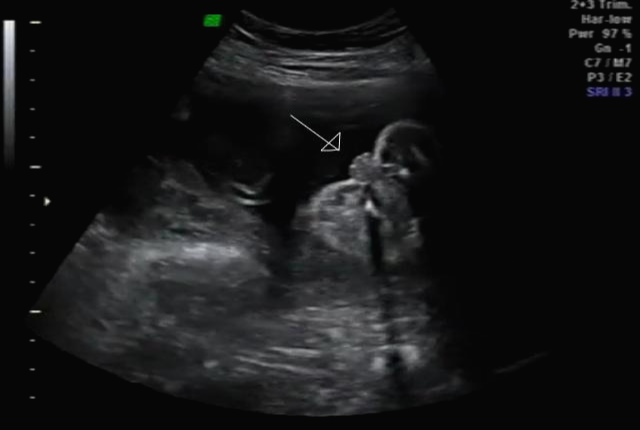

한 달 뒤인 17차 때 다시 사설로 가서 초음파 검사를 받았는데 검사해주시는 분 께서 한참을 보시더라고요~ 그러면서 어떻게 보면 딸 같다고 하셔서... 응? 100프로 아들이라 해서... 다 아들껄로 준비하고 있는데.. 무슨 소리지? 하고 다시 한번 봐달라고 하니 아들이라 하시면서 위에 초음파를 보여주셨어요!

한데 기분이 참 찝찝했어요~ 뭔가 숨기고 있는 듯한.. 정확하지 않는 듯한 느낌 ㅋㅋㅋ... 그래서 임신 17주 차부터 아이 용품 구매하는 걸 중단하고 병원에서 20주 차 정밀 초음파 검사를 기다려 보기로... 가족도 다 아들로 알고 있고 벌써 아들 꺼 처럼 보이는 용품들로 준비했기 때문에 성별 반전이 없기를 기대했어요 ㅠㅠ